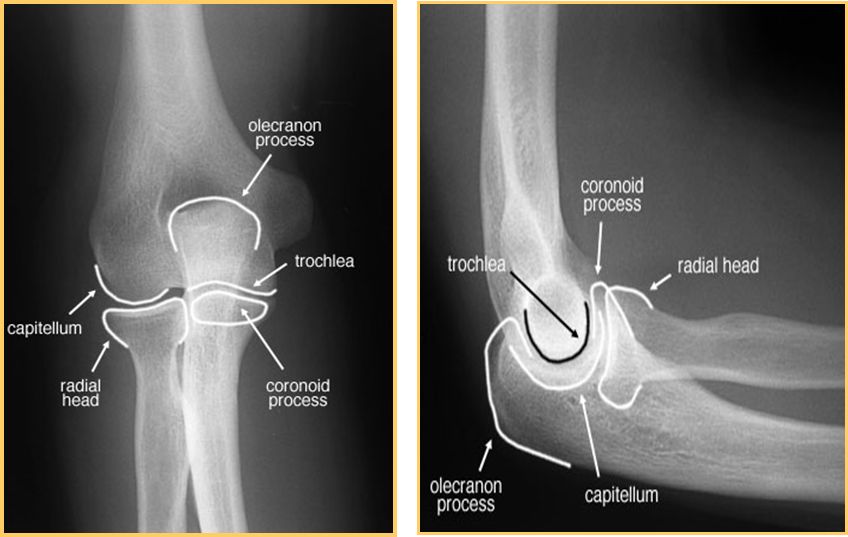

正常肘关节